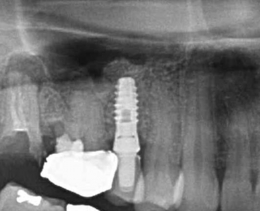

ソケットリフト症例(治療前後のCTもしくはパノラマ写真)

↓

↓